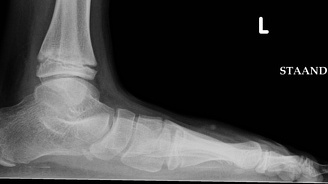

Bàn chân bẹt là hiện tượng bất thường về cấu trúc của bàn chân khi gan bàn chân bằng phẳng, không có độ lõm làm mặt bàn chân tiếp xúc hoàn toàn hoặc gần như hoàn toàn với mặt đất, từ đó gây ra những ảnh hướng đến chức năng của chân. Bàn chân bẹt có thể xảy ra từ khi còn nhỏ hoặc phát triển trong quá trình lớn lên, và có thể ảnh hưởng đến cả nam và nữ.

Mặc dù bàn chân bẹt thường có thể phát hiện qua quan sát bằng mắt thường. Tuy nhiên, để tìm ra nguyên nhân dẫn đến tình trạng này cần thực hiện một số kĩ thuật khác để có thể đưa ra chẩn đoán và phương án điều trị.